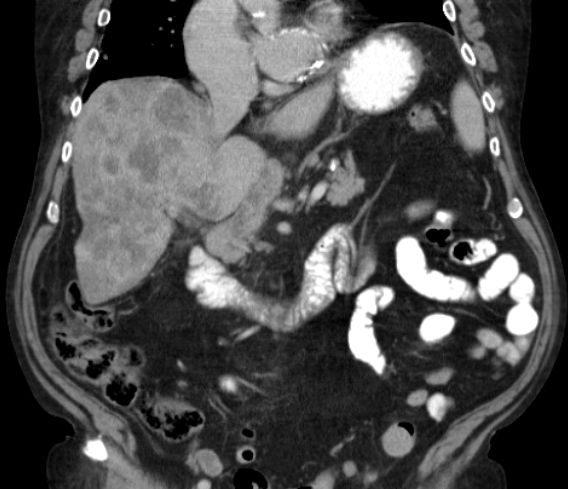

| CT | 61-jähriger trockener Alkoholiker mit bekannter Leberzirrhose und Ascites.

Mehrere Raumforderungen in der Leber. AFP 84. Keine Tumorzellen im Ascites.![]() | ||